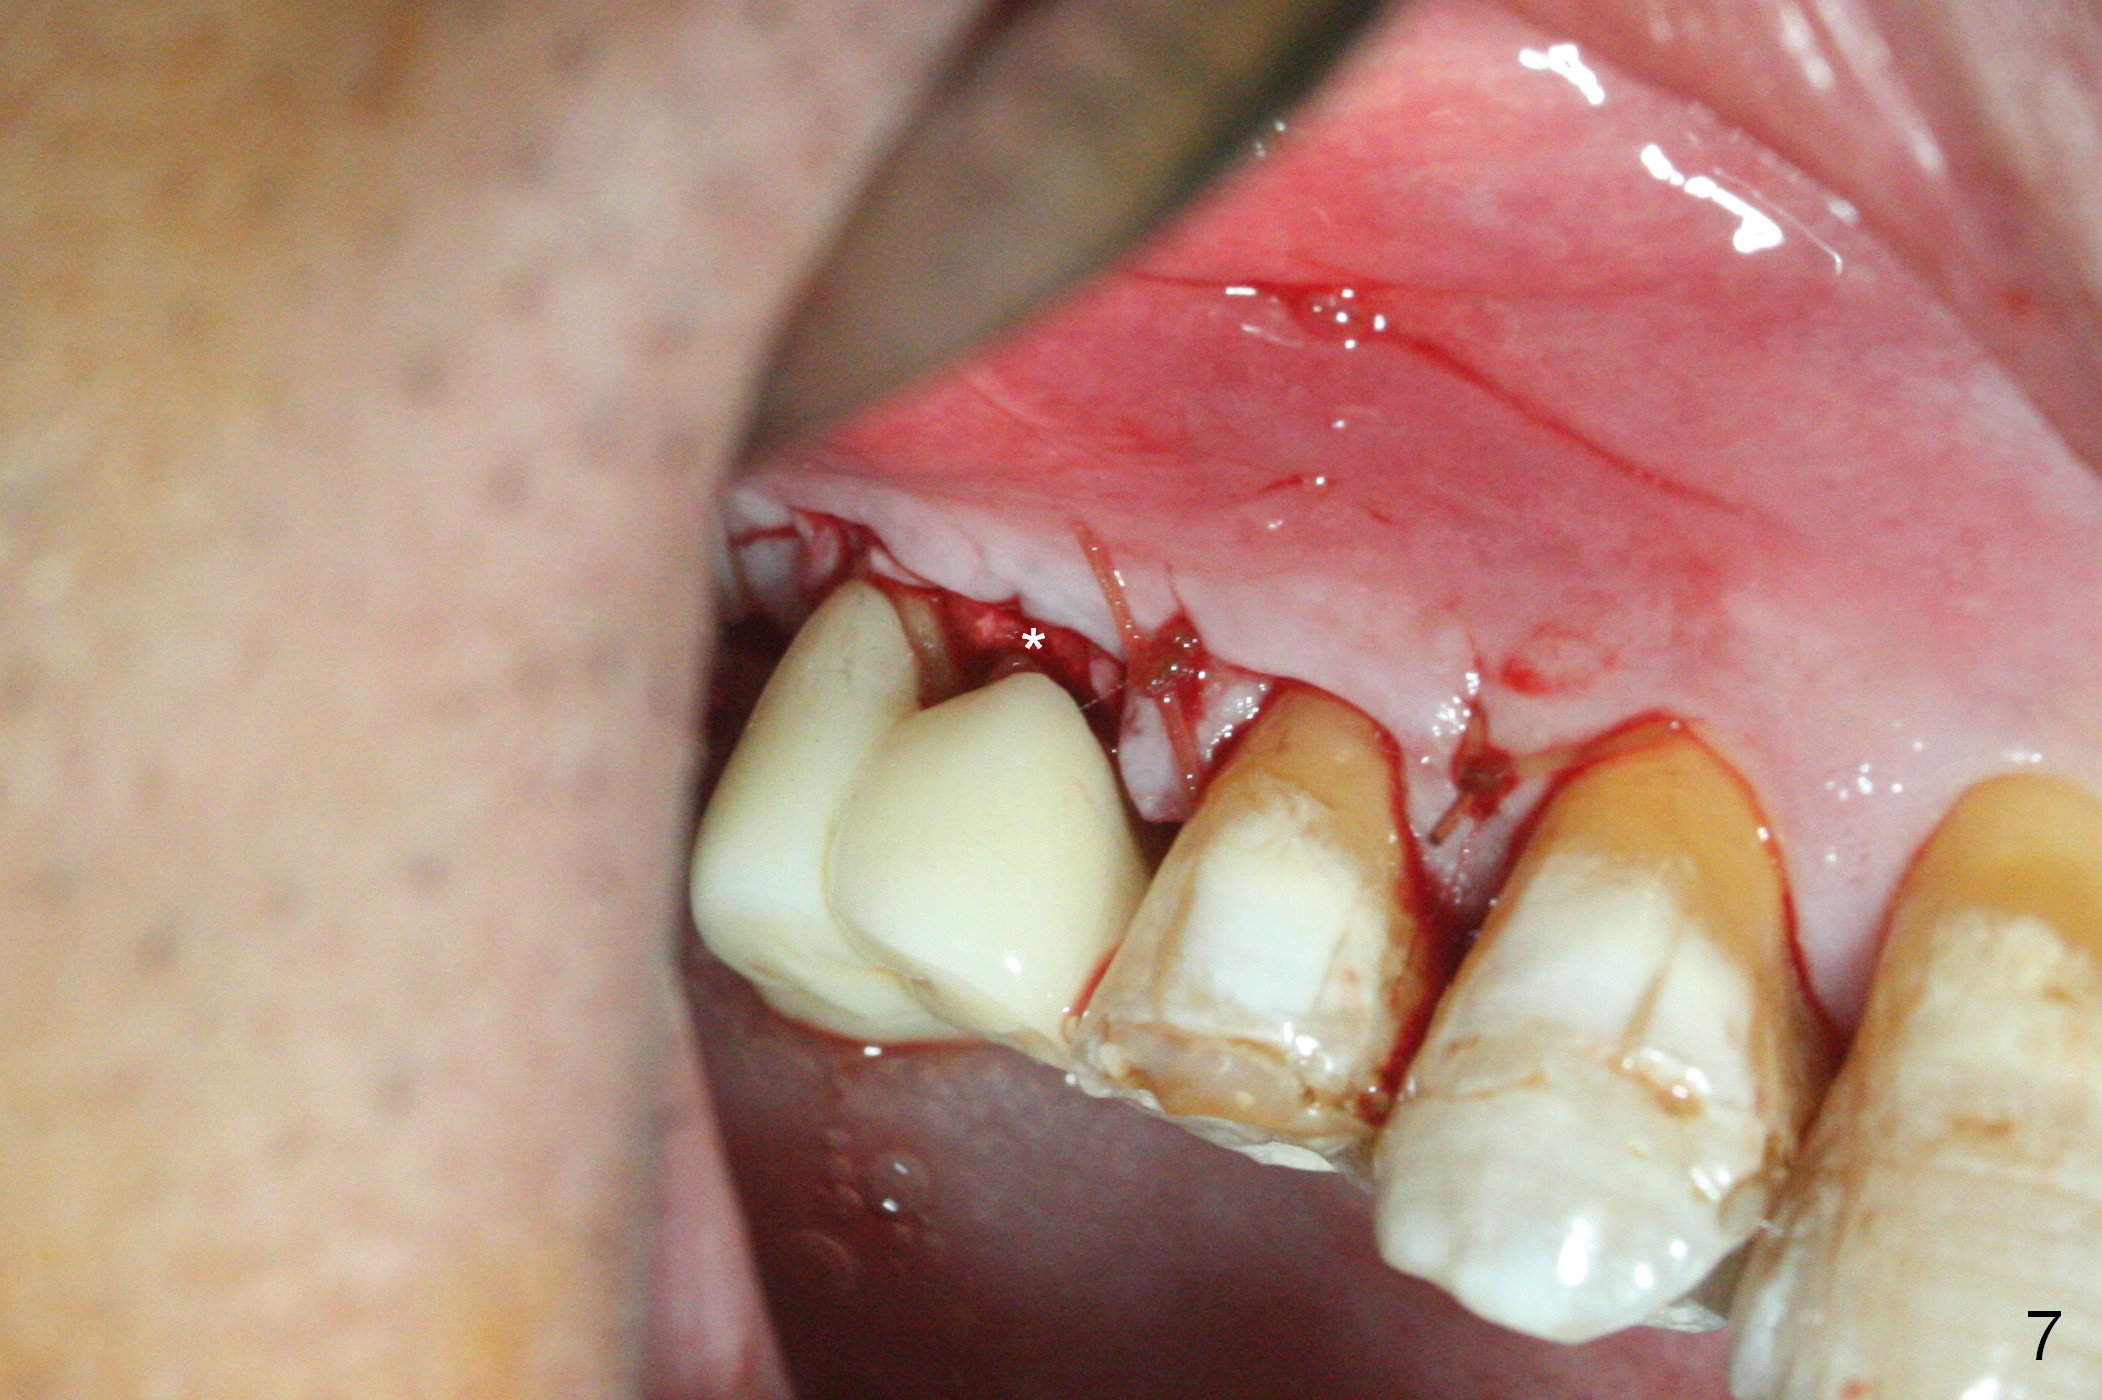

A 56-year-old man has discomfort associated with the tooth #3 one year and a half after root canal therapy (Fig.1: mesiobuccal root vertical fracture). Since an implant is just placed at #19 and another one will be encouraged to be placed at #2 (Fig.2), root amputation may be a valid treatment modality (Fig.3,4). After debridement and Clindamycin topical application, allograft/Osteogen is placed (Fig.5,6 (dashed line)), followed by Osteogen plug (Fig.7 *). Discomfort apparently shifts to the distobuccal root 9 months postop, while the MB defect seems to heal (Fig.8 *). Extraction and implant is expected.